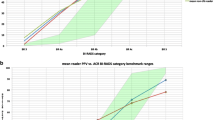

The objective of this study is to retrospectively investigate whether using the newly developed algorithms would improve radiologists’ accuracy for discriminating malignant masses from benign ones on ultrasonographic (US) images. Five radiologists blinded to the histological results and clinical history independently interpreted 226 cases according to the sonographic lexicon of the fourth edition of the Breast Imaging Reporting and Data System and assigned a final assessment category to indicate the probability of malignancy. For each case, each radiologist provided three diagnoses: first with the original images, subsequently with the assistant of the resulting images processed by the proposed CAD algorithms which are called as processed images, and another using the processed images only. Observers’ malignancy rating data were analyzed with the receiver operating characteristic (ROC) curve. For reading only with the processed images, areas under the ROC curve (A z) of each reader (0.863, 0.867, 0.859, 0.868, 0.878) were better than that with the original images (0.772, 0.807, 0.796, 0.828, 0.846), difference of the average A z between the twice reading was significant (p < 0.001). Compared with the results single used processed images, A z of utilizing the combined images were increased (0.866, 0.885, 0.872, 0.894, 0.903), but the difference is not statistically significant (p = 0.081). The proposed CAD method has potential to be a good aid to radiologists in distinguishing malignant breast solid masses from benign ones.